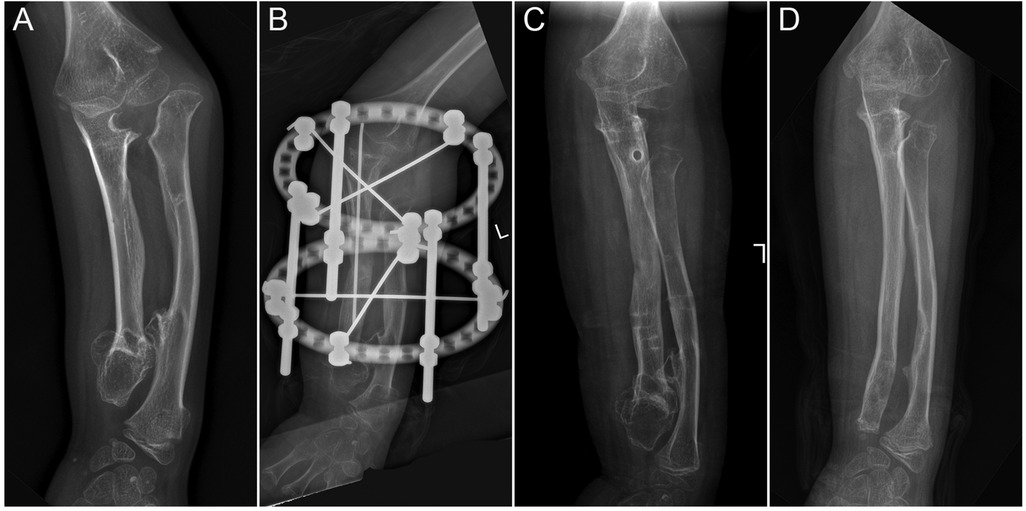

Concentric reduction of the radial head was achieved in all patients with Masada type I deformities and in 9 out of 10 patients with radial head subluxation or dislocation following the ulnar lengthening procedure (Figure 2). During long-term follow-up, one case exhibited recurrent dislocation at the humeroradial joint (Figure 3). A pin tract infection occurred in one pediatric patient but resolved following pin care and oral antibiotic administration. Non-union or neurovascular complications were not observed in any of the patients.

Figure 2

X-ray images of a forearm with four panels labeled A to D. Panel A shows a fractured bone. Panel B displays the application of an external fixator on the fracture. Panel C shows the bone post-fixation with apparent healing. Panel D shows further bone healing, with alignment appearing improved.

Figure 2. The preoperative and postoperative radiographical results of case 12. (A) The preoperative radiograph; (B) postoperative day 1 radiograph; (C) 1-month post-external fixator removement radiograph; and (D) 5-year postoperative radiograph.